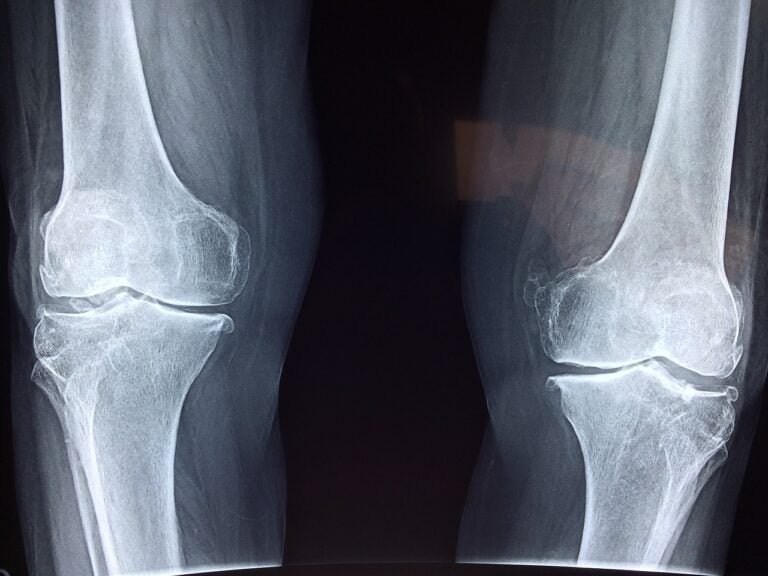

- Imaging tests, including an X-ray of your knee.

The cost of knee replacement surgery ranges from 120,000 to 300,000 pounds and varies depending on the type of joint required, which is determined based on the degree and shape of knee joint roughness in the images, the presence of severe joint curvature, and the patient’s weight.